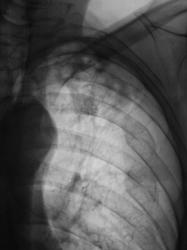

Пациент находится на диспансерном учете в туб. кабинете, по поводу инфильтративного туберкулёза верхней доли левого лёгкого, получает специфическое лечение. Пациент направлен в рентгеновский кабинет для рентгенологического исследования исследования органов грудной полости "в динамике". Проведено стандартное исследование.

Для сравнения приводятся изображения, произведенные чуть больше года тому.